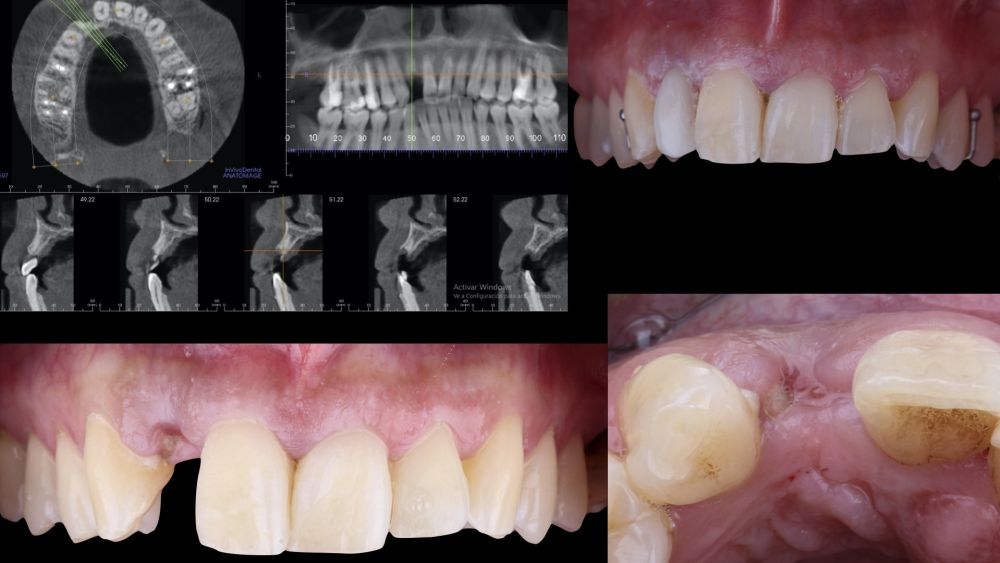

* Phase II: healing proceeded without complications. After 5 months from the alveolar preservation surgery, guided implant surgery was planned at position 1.2 (Figure 2). For this purpose, a DICOM file from cone beam computed tomography (CBCT) and an STL file obtained from scanning with an intraoral optical scanner were used. Using this information, a dental support surgical guide was fabricated (Figure 3). The surgical guide was anchored onto the teeth and guided the preparation of the implant bed and the placement of the implant. The guided surgery technique consisted of flap surgery, preparing and inserting the implant (3.5 x 11.5 mm) according to the standardised Nobel Active® guided surgery protocol (Nobel Biocare AB, Gothenburg, Sweden). Once implant 1.2 was placed,a gingival graft composed of epithelium and connective tissue from the palatal masticatory mucosa was obtained. Subsequently, the superficial epithelial layer of this graft was deepithelialised extraorally using a 15C scalpel blade in order to obtain a connective tissue graft from the underlying layer18.

The site where the surgery was performed (implant 1.2), together with its complete arch, was scanned using an

intraoral optical scanner at different time points; three

weeks before the surgery (T0), immediately after the surgery (T1), and one and a half months post-surgery (T2). The generated digital models were exported and saved as STL files to be subsequently imported into image analysis software (Geomagic® Control X™; 3D

Systems, Rockhill, SC). An analysis of preoperative (T0) versus postoperative (T1 and T2) thickness changes was conducted. These longitudinal thickness changes were analysed on the vestibular aspect of the implantsupported crown using the “3D Compare” function, which

enabled the creation of a colour map following model superimposition to quantitatively assess the variations occurring in the intervention areas. The colour map ranges from +3 mm to -3 mm, with a tolerance of ± 0.15mm, and is interpreted as follows: green areas correspond

to perfect alignment of the models; red, orange, and yellow colours are interpreted as volume gain, while dark and light blue colours respectively represent volumetric loss (Figures

8 and 9). Subsequently, a rectangular region of interest was designed to study the intervention area, where linear changes of the peri-implant mucosa were evaluated (Figures 8 and 9). The horizontal extension of the region of interest encompassed both papillae (mesial and distal), covering the marginal contour of the implant crown up to the marginal surface of the adjacent teeth. To report the results of interest, points were identified on the horizontal plane previously designed on the vestibular aspect of the implant, starting from the mesial and extending 0.5 mm distally. Positive values indicated that the peri-implant soft tissues were located more buccally (> thickness), whereas negative values indicated that the peri-implant soft tissues were located more palatally (< thickness).